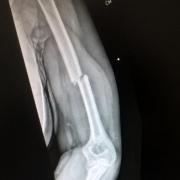

I had been really looking forward to day 17 – Thursday 20th July was my first appointment at the fracture clinic at Frimley Park. I say looking forward; I suppose there was an element of trepidation mixed in with the curiosity. I hoped I’d find out how my arm was progressing, if the bones were lining up, and above all that I’d be offered a more robust brace of some kind to give my wobbly arm more protection. I was also slightly nervous that there would be pain, that they’d try to manipulate my arm in some painful way (why, I have no idea?) or that fitting a new brace might hurt. Also that they’d look and say ‘I’m sorry, your bones are not going to meet up’. Totally irrational but that’s the nature of fear and the unknown!

In the event it was all quite quick. We were called in promptly and the doctor took a quick look and organised a chitty for an  x-ray and a brace to be fixed (relief!), promising we could come back to ask questions afterwards. We moved into the plaster room as instructed but a nurse asked me to climb into a chair with a raised armrest and I stared at in fear, saying “I don’t think I can lift my arm onto there!”. She quickly realised we were in the wrong place and the consultant came back to see us again to explain he’d only been at Frimley a week and he’d got it wrong – an x-ray today was too early to see improvement. I needed a moulded plastic brace fitting though – so we were sent off to occupational therapy to get one sorted.

Before we left I checked a few things with him – pain relief, swelling, likely timescales. I don’t think we learned anything new. He said we’d have to experiment with the pain meds to get it right, and gave 10 to 12 weeks before I’d be able to have the brace removed. He said there was a possibility the union wouldn’t be perfect but up to 30% displacement was normal and my arm would regain full functionality. I was to return in two weeks to get the update x-ray.